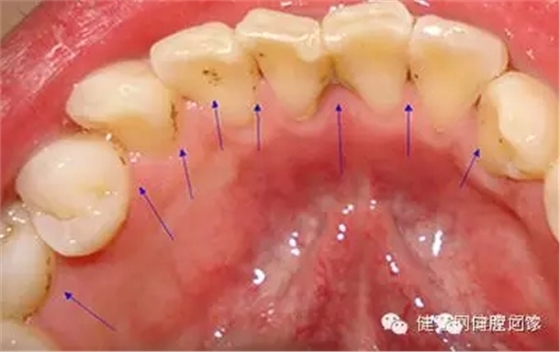

牙垢也叫牙菌斑,是附著在牙齦冠部、頸部及牙縫間的污垢。牙垢主要是食物殘渣、口腔黏膜脫落的上皮、唾液及細(xì)菌混合而成。牙垢久積,容易鈣化成牙結(jié)石。牙垢沉積的多少、快慢,因人而異,與口腔衛(wèi)生習(xí)慣、食物成分、咀嚼習(xí)慣、牙齒排列及機(jī)體代謝情況有關(guān),最快可形成于潔牙后的48小時。 牙垢可能造成哪些危害?

2. 牙周疾病。牙垢久積,容易形成牙結(jié)石,牙石的存在會妨礙口腔衛(wèi)生,促使菌斑更多地形成,牙石本身也會吸附更多的細(xì)菌和毒素,造成牙齦充血、水腫,產(chǎn)生牙齦炎、牙周炎等問題;